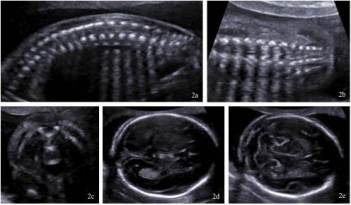

Základní metodou screeningu rozštěpových vad neurální trubice je v těhotenství klasické dvojrozměrné ultrazvukové vyšetření (obrázek č. 2 a 3). Upřesnit diagnostiku může umožnit trojrozměrný ultrazvuk (obrázek č. 3) a magnetická rezonance (obrázek č. 4).

Obrázek č. 2.: Standardní dvojrozměrné (2D) ultrazvukové vyšetření páteře a lebky plodu. Vyšetření páteře plodu v tzv. sagitální (2a), transversální (2b) a koronální (2c) rovině a vyšetření lebky plodu v transversální rovině (2d, a, e).

(Foto: MUDr. Veronika Frisová, Profema)